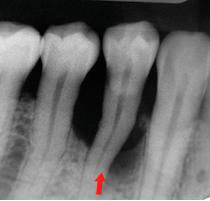

治療前牙周有環狀骨缺損,牙齒動搖。

治療後12個月牙周骨再生,牙齒穩固。